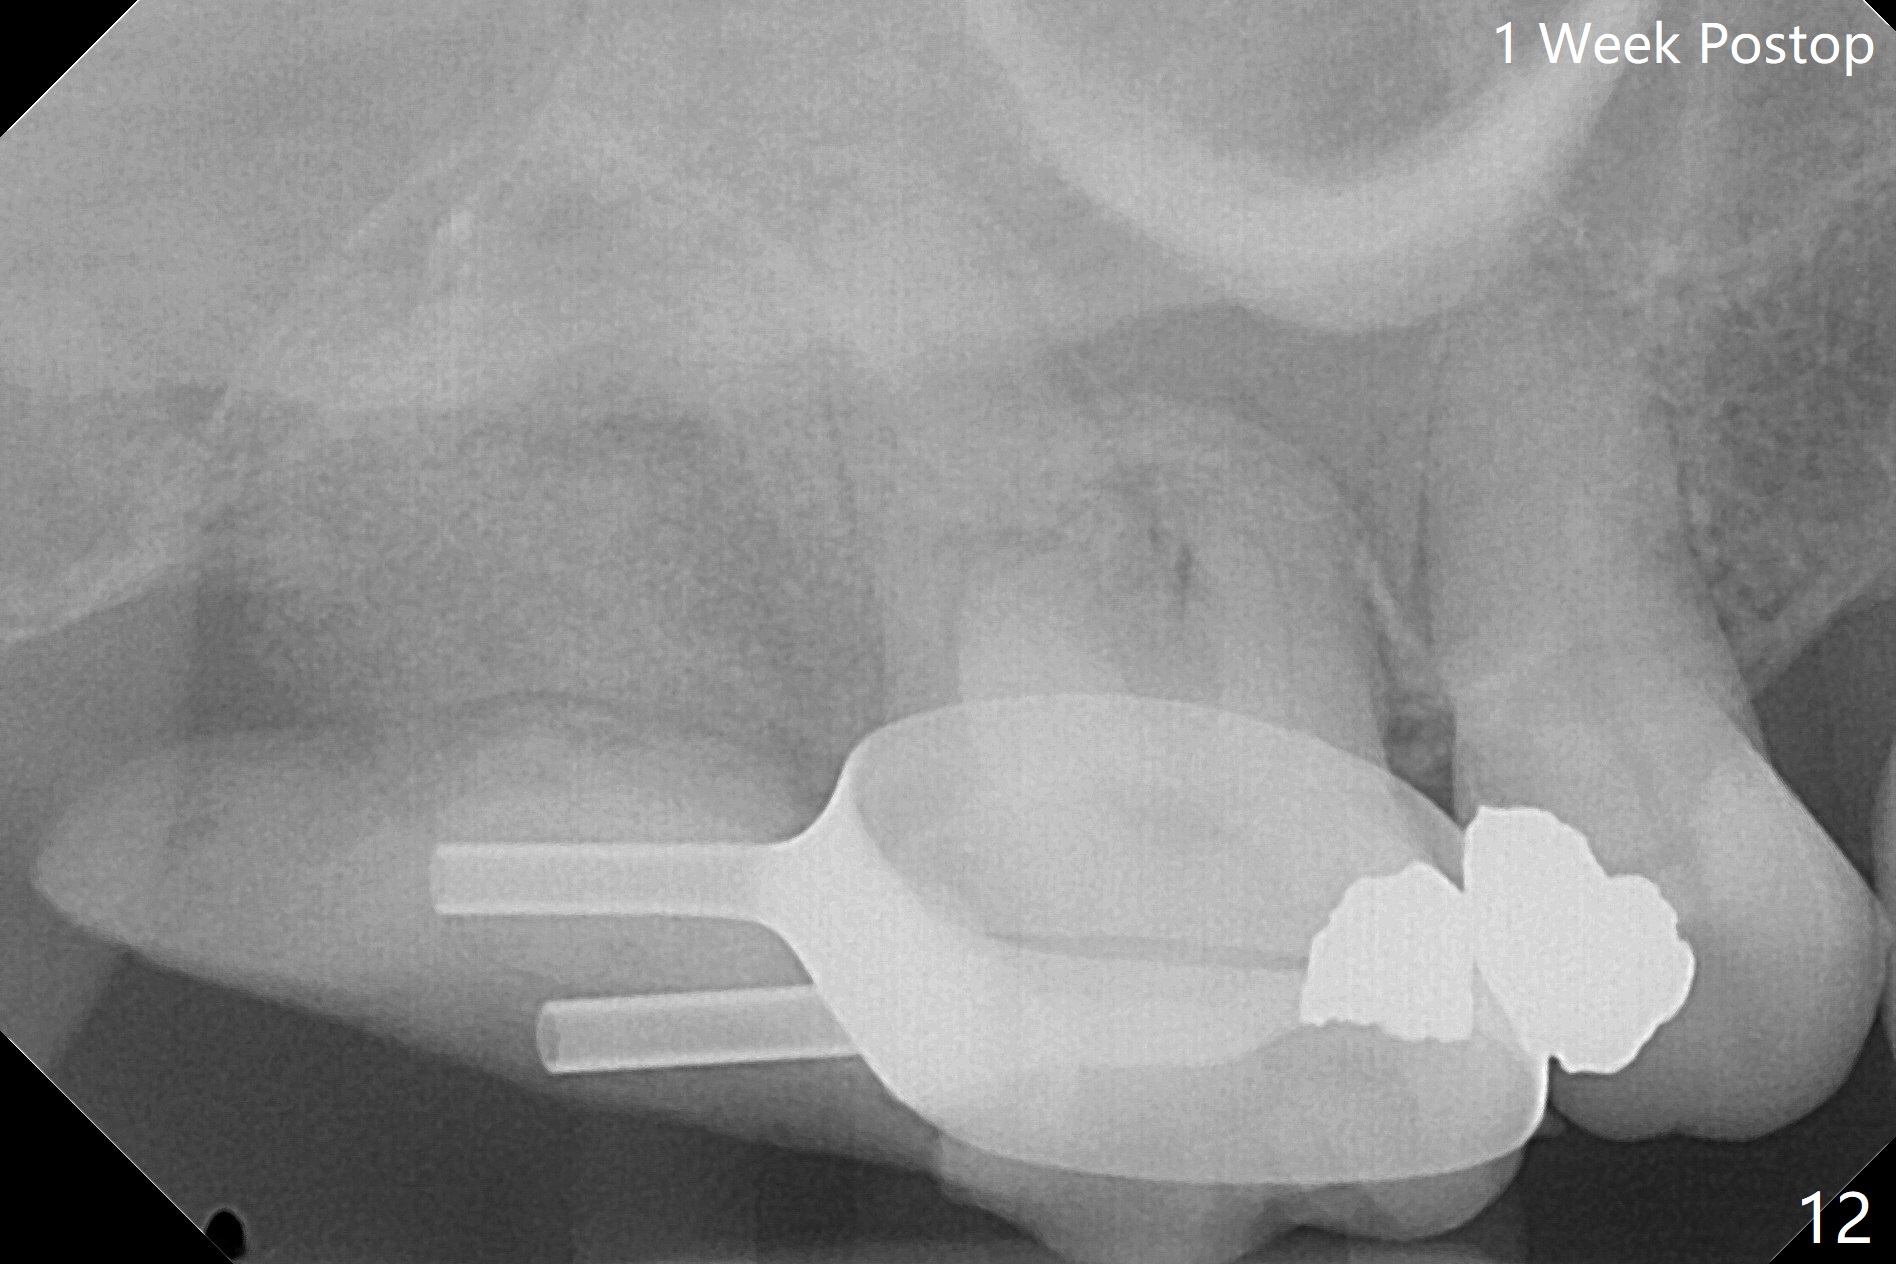

第二磨牙位点保留后,牙周敷料容易脱落,尤其上颌,本文介绍一种方法增加固位。右上七严重牙髓牙周综合征,拔出后使用刮匙除去骨面肉芽组织,颊侧骨板缺失,附着在颊侧粘骨膜上的肉芽组织使用一种叫Stieglitz angled, diamond splinter forceps (德国产,图一,二)撕下来。彻底清除炎性组织必须多次刮治,之间塞入带有灭滴灵(图三:粉剂)和1比50,000肾上腺素局麻药纱布(图四)止血,取出纱布,牙槽窝视野好,继续去除残余的肉芽组织。牙槽窝底部穿孔,用无齿刮匙稍微扩大穿孔后,使用图五下面小的骨粉输送器,将少量骨粉(粘性)送到穿孔处,推入上颌窦(图七:S),之后使用大的骨粉输送器(图五上面),把大量骨粉送到牙槽窝,使用图六上面大的,长的充填器,压实骨粉(图七),骨粉表面放置PRF膜和不可吸收膜(图八),在第一磨牙时安置粘固一个间隙维持器(图九,十),最后铺上牙周敷料(图十一),检查咬合空间,没有干扰。There are sign and symptom of sinusitis 1 week postop; large amount of bone graft retains in the socket by the periodontal dressing and spacer (Fig.12). The sinus membrane (Fig.7 immediate postop) thickens 1 week postop (Fig.13). Augmentin and Medrol Dose Pak are prescribed. 上颌窦炎一周后消失,腭侧牙周敷料丢失,伤口好像正常愈合(图十四)。术后三周牙周敷料由于大量水枪冲洗脱落(图十五)。因为病人需要离城两个月,间隙保持器撤除(图十六),不可吸收膜腭侧稍微外翻 (<),可能有利于术后五周自行脱落。No Deviation SP 下一个病例 位点保留后Xin 导板与张口度 第一磨牙即种 Wei, DDS, PhD, MS 1st edition 09/17/2020, last revision 04/30/2021